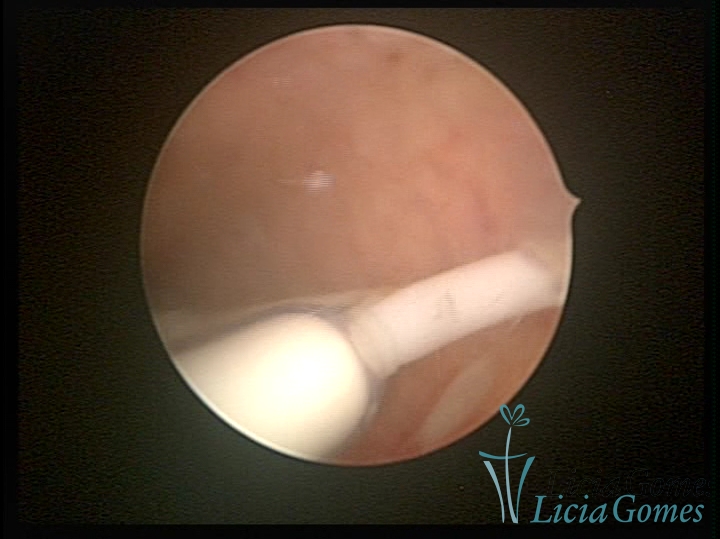

Canal cervical com fio do DIU